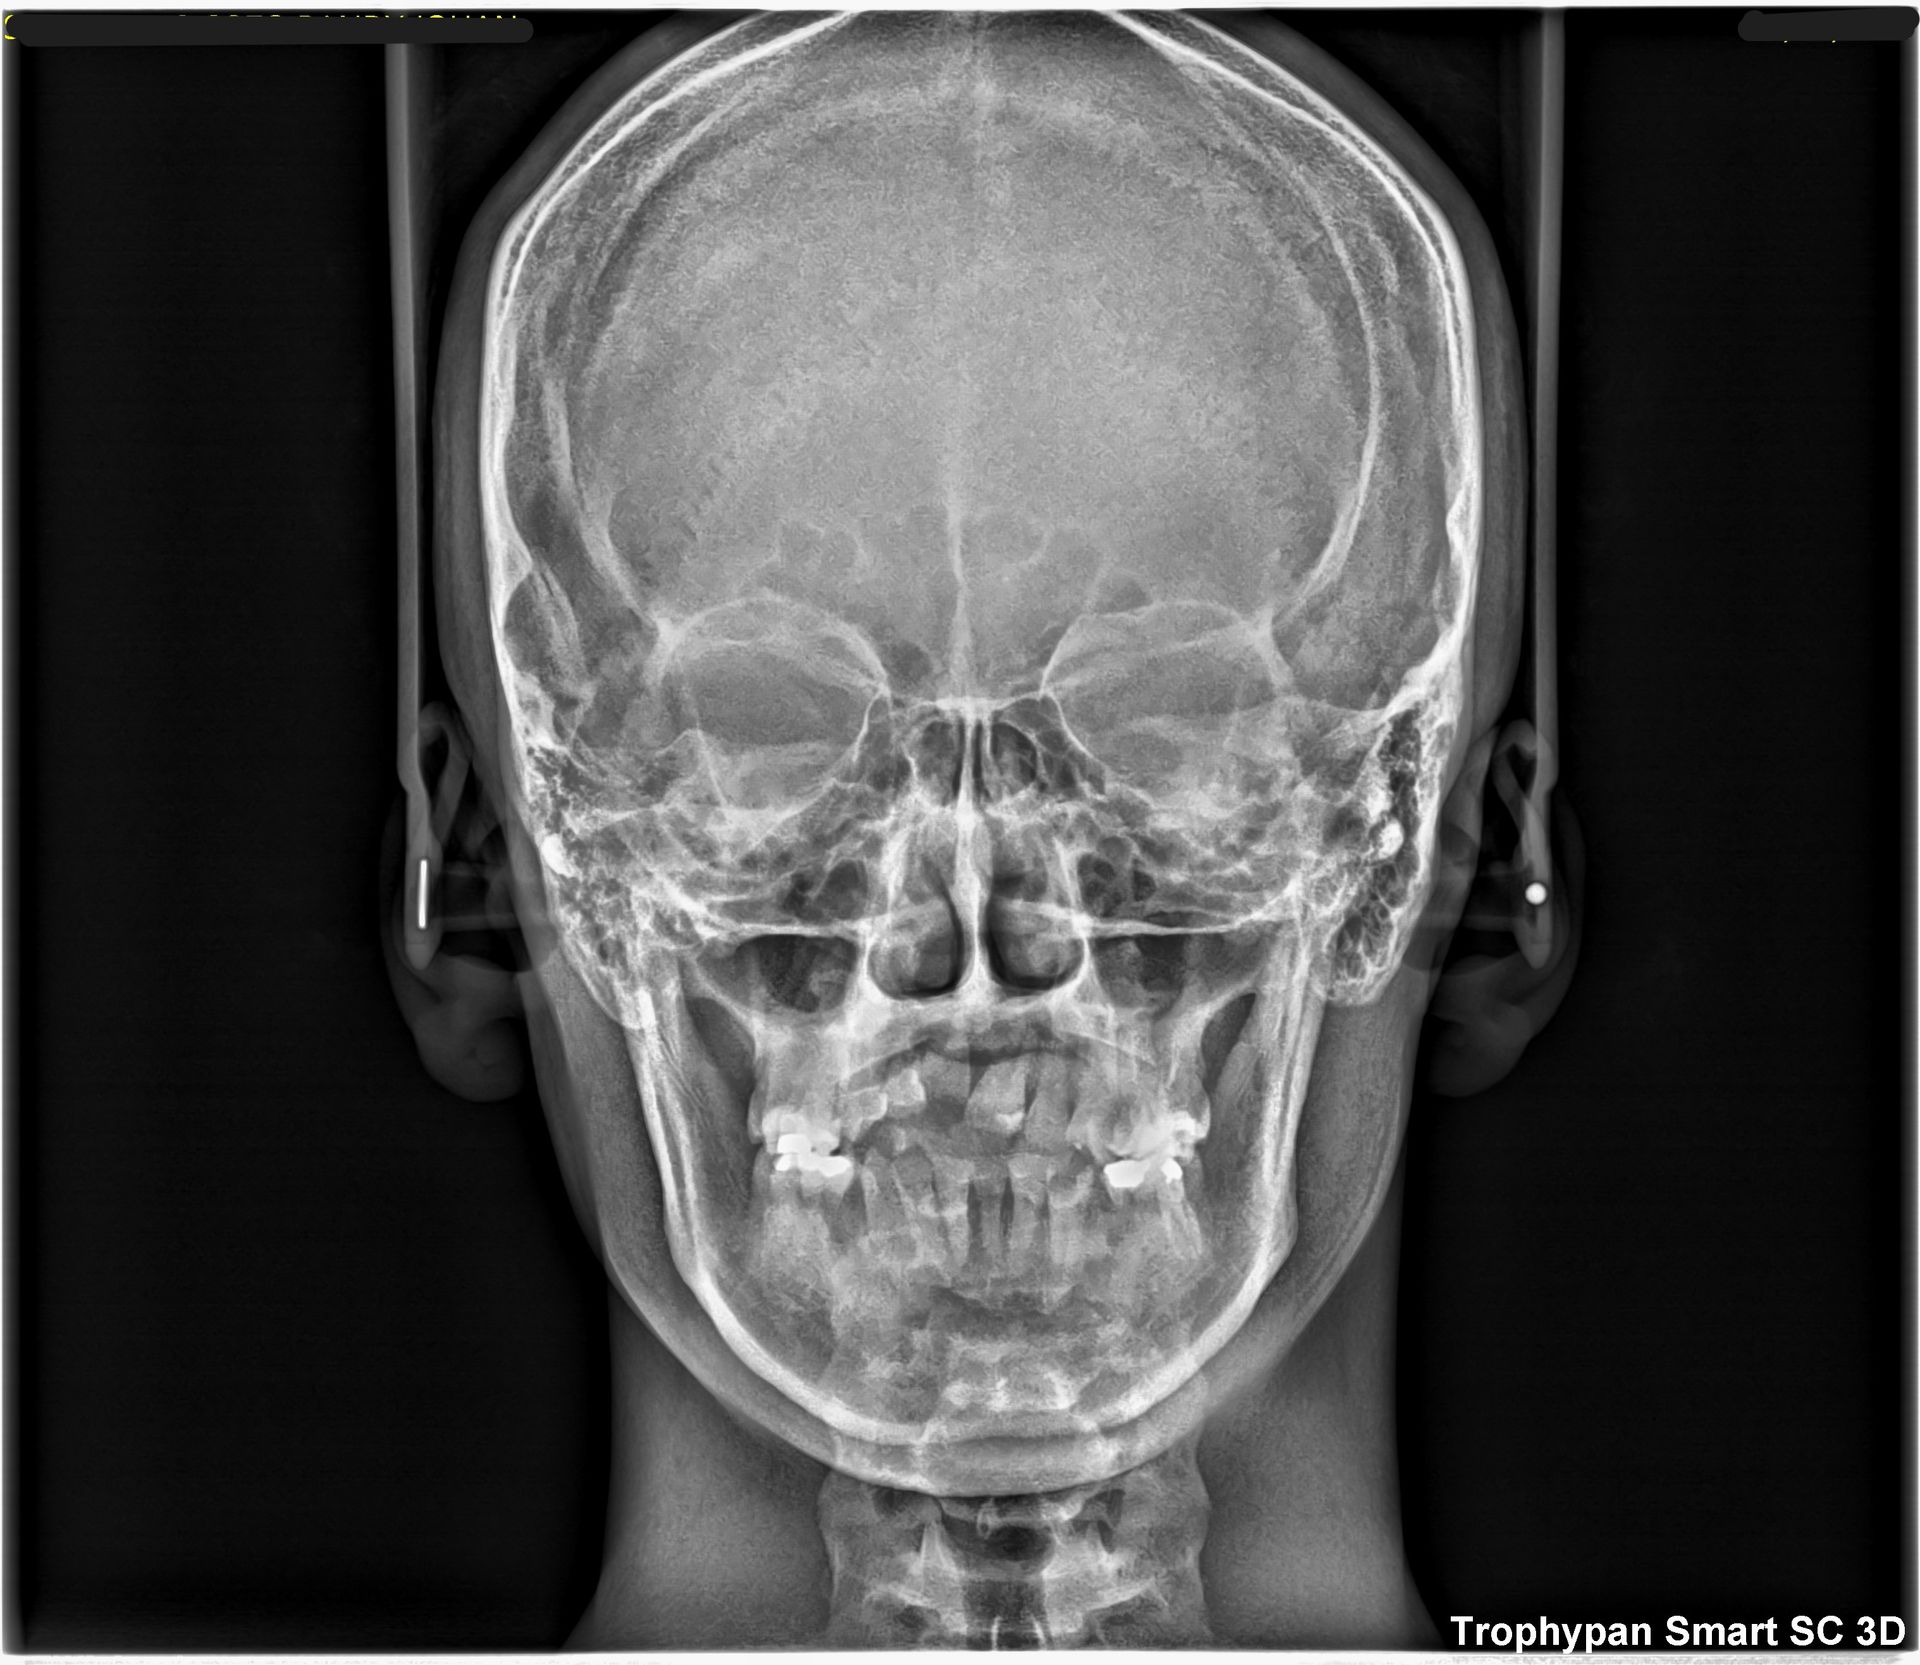

Uno de nuestros principales servicios es la adquisición de imágenes dentales 2D y 3D, fundamentales para un diagnóstico preciso y una planificación adecuada de tratamientos dentales.

Contamos con tecnología avanzada que nos permite obtener imágenes claras y detalladas de la boca y los tejidos circundantes, lo que es crucial para evaluar la salud dental y detectar posibles problemas.